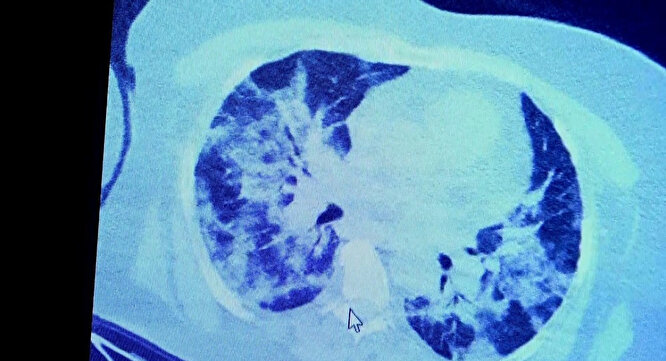

Koronavirüs testi pozitif çıkan hastaların ilaç kullandığı ve kullanmadığı durumda akciğerlerinin hali görüntülendi. Prof. Dr. Şevket Özkaya, bir hafta ilaç kullanmayan bir pozitif hastanın akciğer tomografisini inceledi. Hasta pozitif haldeyken ilk akciğer tomografisine bakıldı. Tomografide akciğerlerdeki tutulmanın az olduğu gözlemlendi. Sonra da aynı hastanın verilen ilaçları kullanmamış ve 1 hafta boyunca tedaviye uymamış haldeki akciğer tomografisine bakıldı. Sonuç ise ilaç kullanımının önemini ortaya çıkardı.

VM Medical Park Samsun Hastanesi’nde görev yapan Göğüs Hastalıkları Kliniği’nden Prof. Dr. Şevket Özkaya da bir hafta ilaç kullanmayan bir pozitif hastanın akciğer tomografisini inceledi. Hasta pozitif haldeyken ilk akciğer tomografisine bakıldı. Tomografide akciğerlerdeki tutulmanın az olduğu gözlemlendi. Akabinde aynı hastanın verilen ilaçları kullanmamış ve 1 hafta boyunca tedaviye uymamış haldeki akciğer tomografisine bakıldı. Sonuç ise ilaç kullanımının önemini ortaya çıkardı. Hastanın akciğer tomografisinde yaygın buzlu camların ve hava yollarının hava yerine ciddi şekilde sıvı ile dolduğu gözlemlendi.

Akciğer tomografisinde oluşan değişim ile ilgili bilgi veren Prof. Dr. Şevket Özkaya, "Ekranda 55 yaşında bir kadın hastamızın filmini görüyorsunuz. Bu kadın hastamız acil servisimize ateş şikâyetiyle geldi ve korona virüsünden şüphe ettik. Testini yaptığımızda ise testin sonucu pozitif geldi.

Tomografi çektiğimiz zaman akciğerlerinde henüz ciddi bir tutulum görünmezken hastamız 55 yaşında olduğu için her an ilerleyebilir korkusuyla Sağlık Bakanlığımızın önerdiği ilaçları ve reçeteyi hastanemizden kendisine verdik. Hasta kendini evde karantinaya aldı fakat sonradan öğrendik ki tereddüt ettiği için ilaçlarını kullanmayarak kendini evde tedavisiz bırakmış. Yaklaşık bir hafta sonra aynı hasta acil servisimize bu sefer solunum yetmezliği şikâyetiyle geldi. Solunum yetmezliği gelişince hastanın akciğer tomografisinde ‘buzlu cam’ dediğimiz ve daha ileri konsolide alanların oluştuğunu gördük.

Yaygın akciğer harabiyeti dediğimiz bir tablo oluşmuştu. Bu durumda hastada solunum yetmezliği olduğu için yoğun bakıma almak zorunda kaldık" dedi.